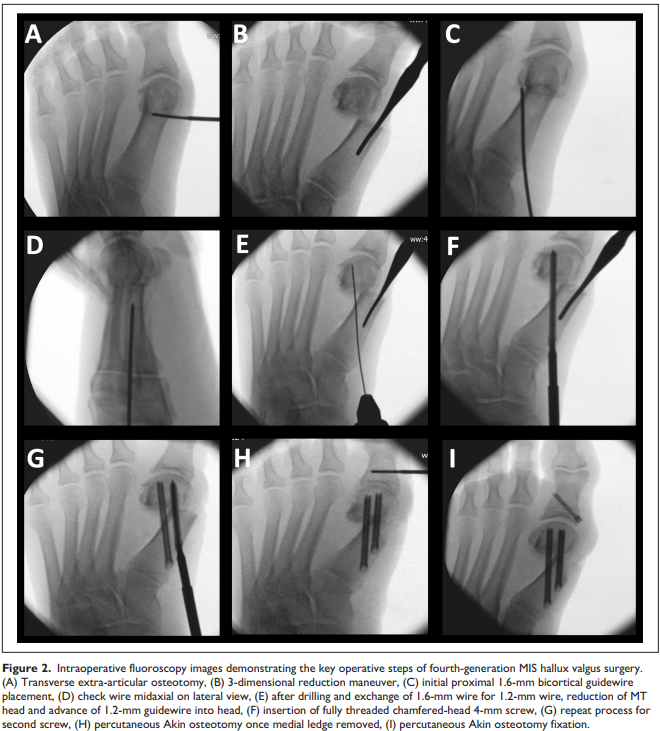

Fourth-Generation Minimally Invasive Hallux Valgus Surgery With Metaphyseal Extra-Articular Transverse and Akin Osteotomy (META): 12 Month Clinical and Radiologic Results 라는 제목의 논문입니다.

META는 Metaphyseal Extra-articular Transverse and Akin Osteotomy 를 뜻합니다.

사실 용어에서 Minimal Invasive라는 약자가 사라졌기 때문에 오히려 MITA (Minimally Invasive Transverse and Akin Osteotomy) 라고 불리는 것이 맞을 것 같습니다.

수술방법과 사진은 동일한데 절골면이 transverse 합니다. 이렇게 transverse 하게 되면 쉬울 뿐더러, 절골면이 전반적으로 근위부의 cortical bone 면적이 넓어져 cortex가 유지가 잘 되어 유리한 측면이 있습니다. IMA(Intermetatarsal angle) 교정을 매우 빠르게 가져올 수 있습니다.

3세대와 비교하여 특별하게 크게 달라진 것은 없으나 임상적 예후가 좋은 것으로 논문이 나왔으니 앞으로는 이러한 수술법도 많이 늘어날 수 있을 것 같습니다. 1991년 이런 미세 수술이 발명된 이후, 이런 작은 발전들이 모여 현대 수술기법이 되었을 것 입니다. Akin 은 기존 그대로 open wedge style로 추가적인 HVA을 교정해 줍니다.